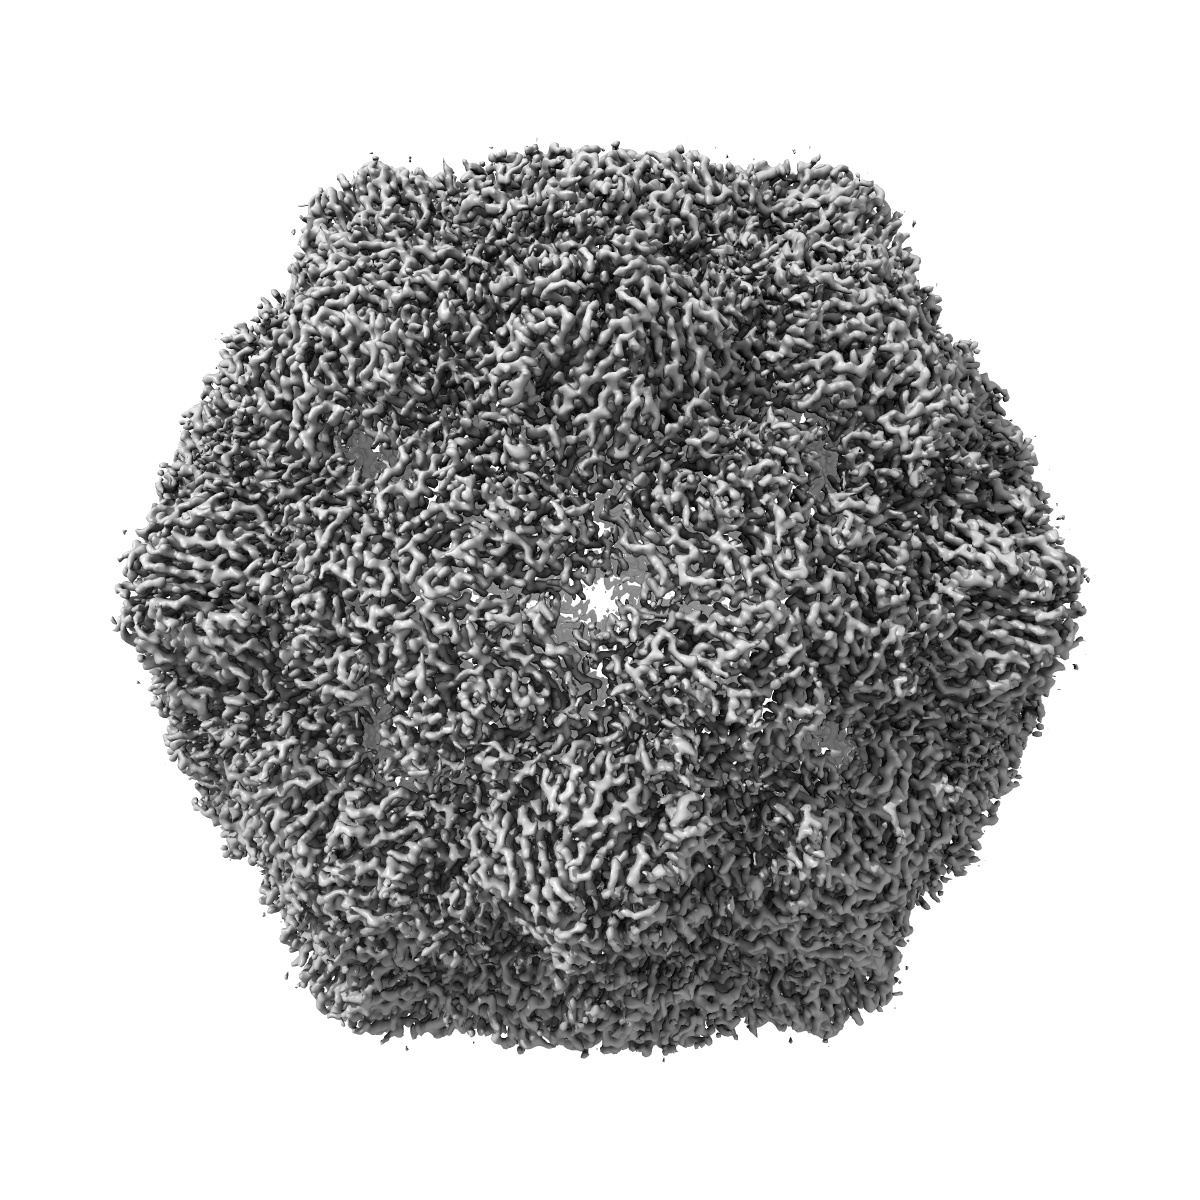

EMD-50112

Poliovirus type 1 (strain Mahoney) expanded conformation stabilised virus-like particle (PV1 SC6b) from a mammalian expression system

Single-particle3.0 Å

Recombinant expression systems for production of stabilised virus-like particles as next-generation polio vaccines.

(2025) Nat Commun , 16 , 831 - 831